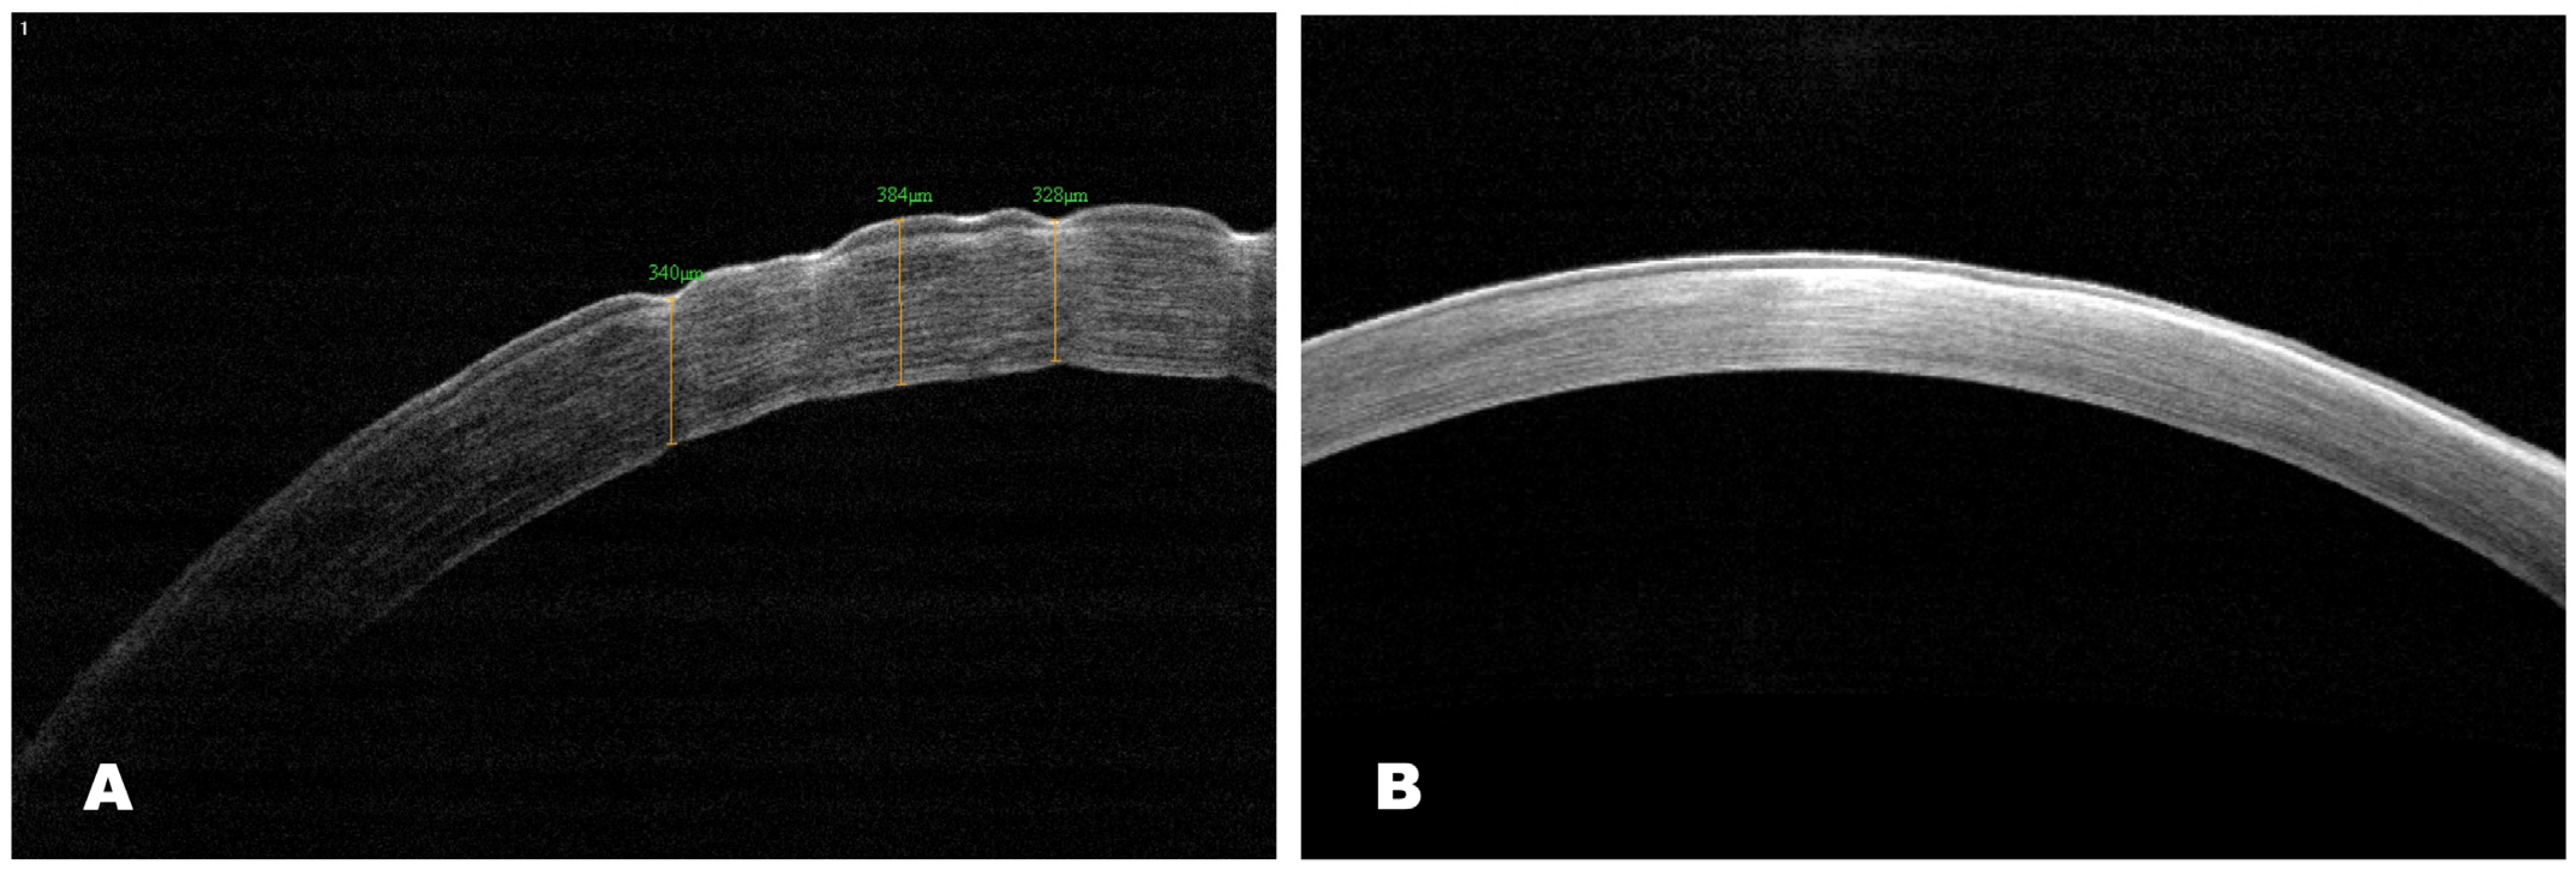

AS-OCT

Data from the AS-OCT 30 days after treatment showed the restoration of corneal contours with the preservation of slight superficial opacity in the experimental group. The epithelialization was complete, and the corneal surface was smooth.

In the same period, the corneal surface was rough and slightly thickened, with the preservation of erosion and edema (Figure 12). The results matched the biomicroscopic picture.

Figure 12. AS-OCT images. Scans of central cornea: (A) scan shows epithelial defects with corneal irregularity, subepithelial corneal opacity with hyperreflective areas in the control group; (B) AS-OCT scan shows restoration of corneal epithelial integrity with superficial haze in the experimental group.

Biomedicines 12 00101 g012